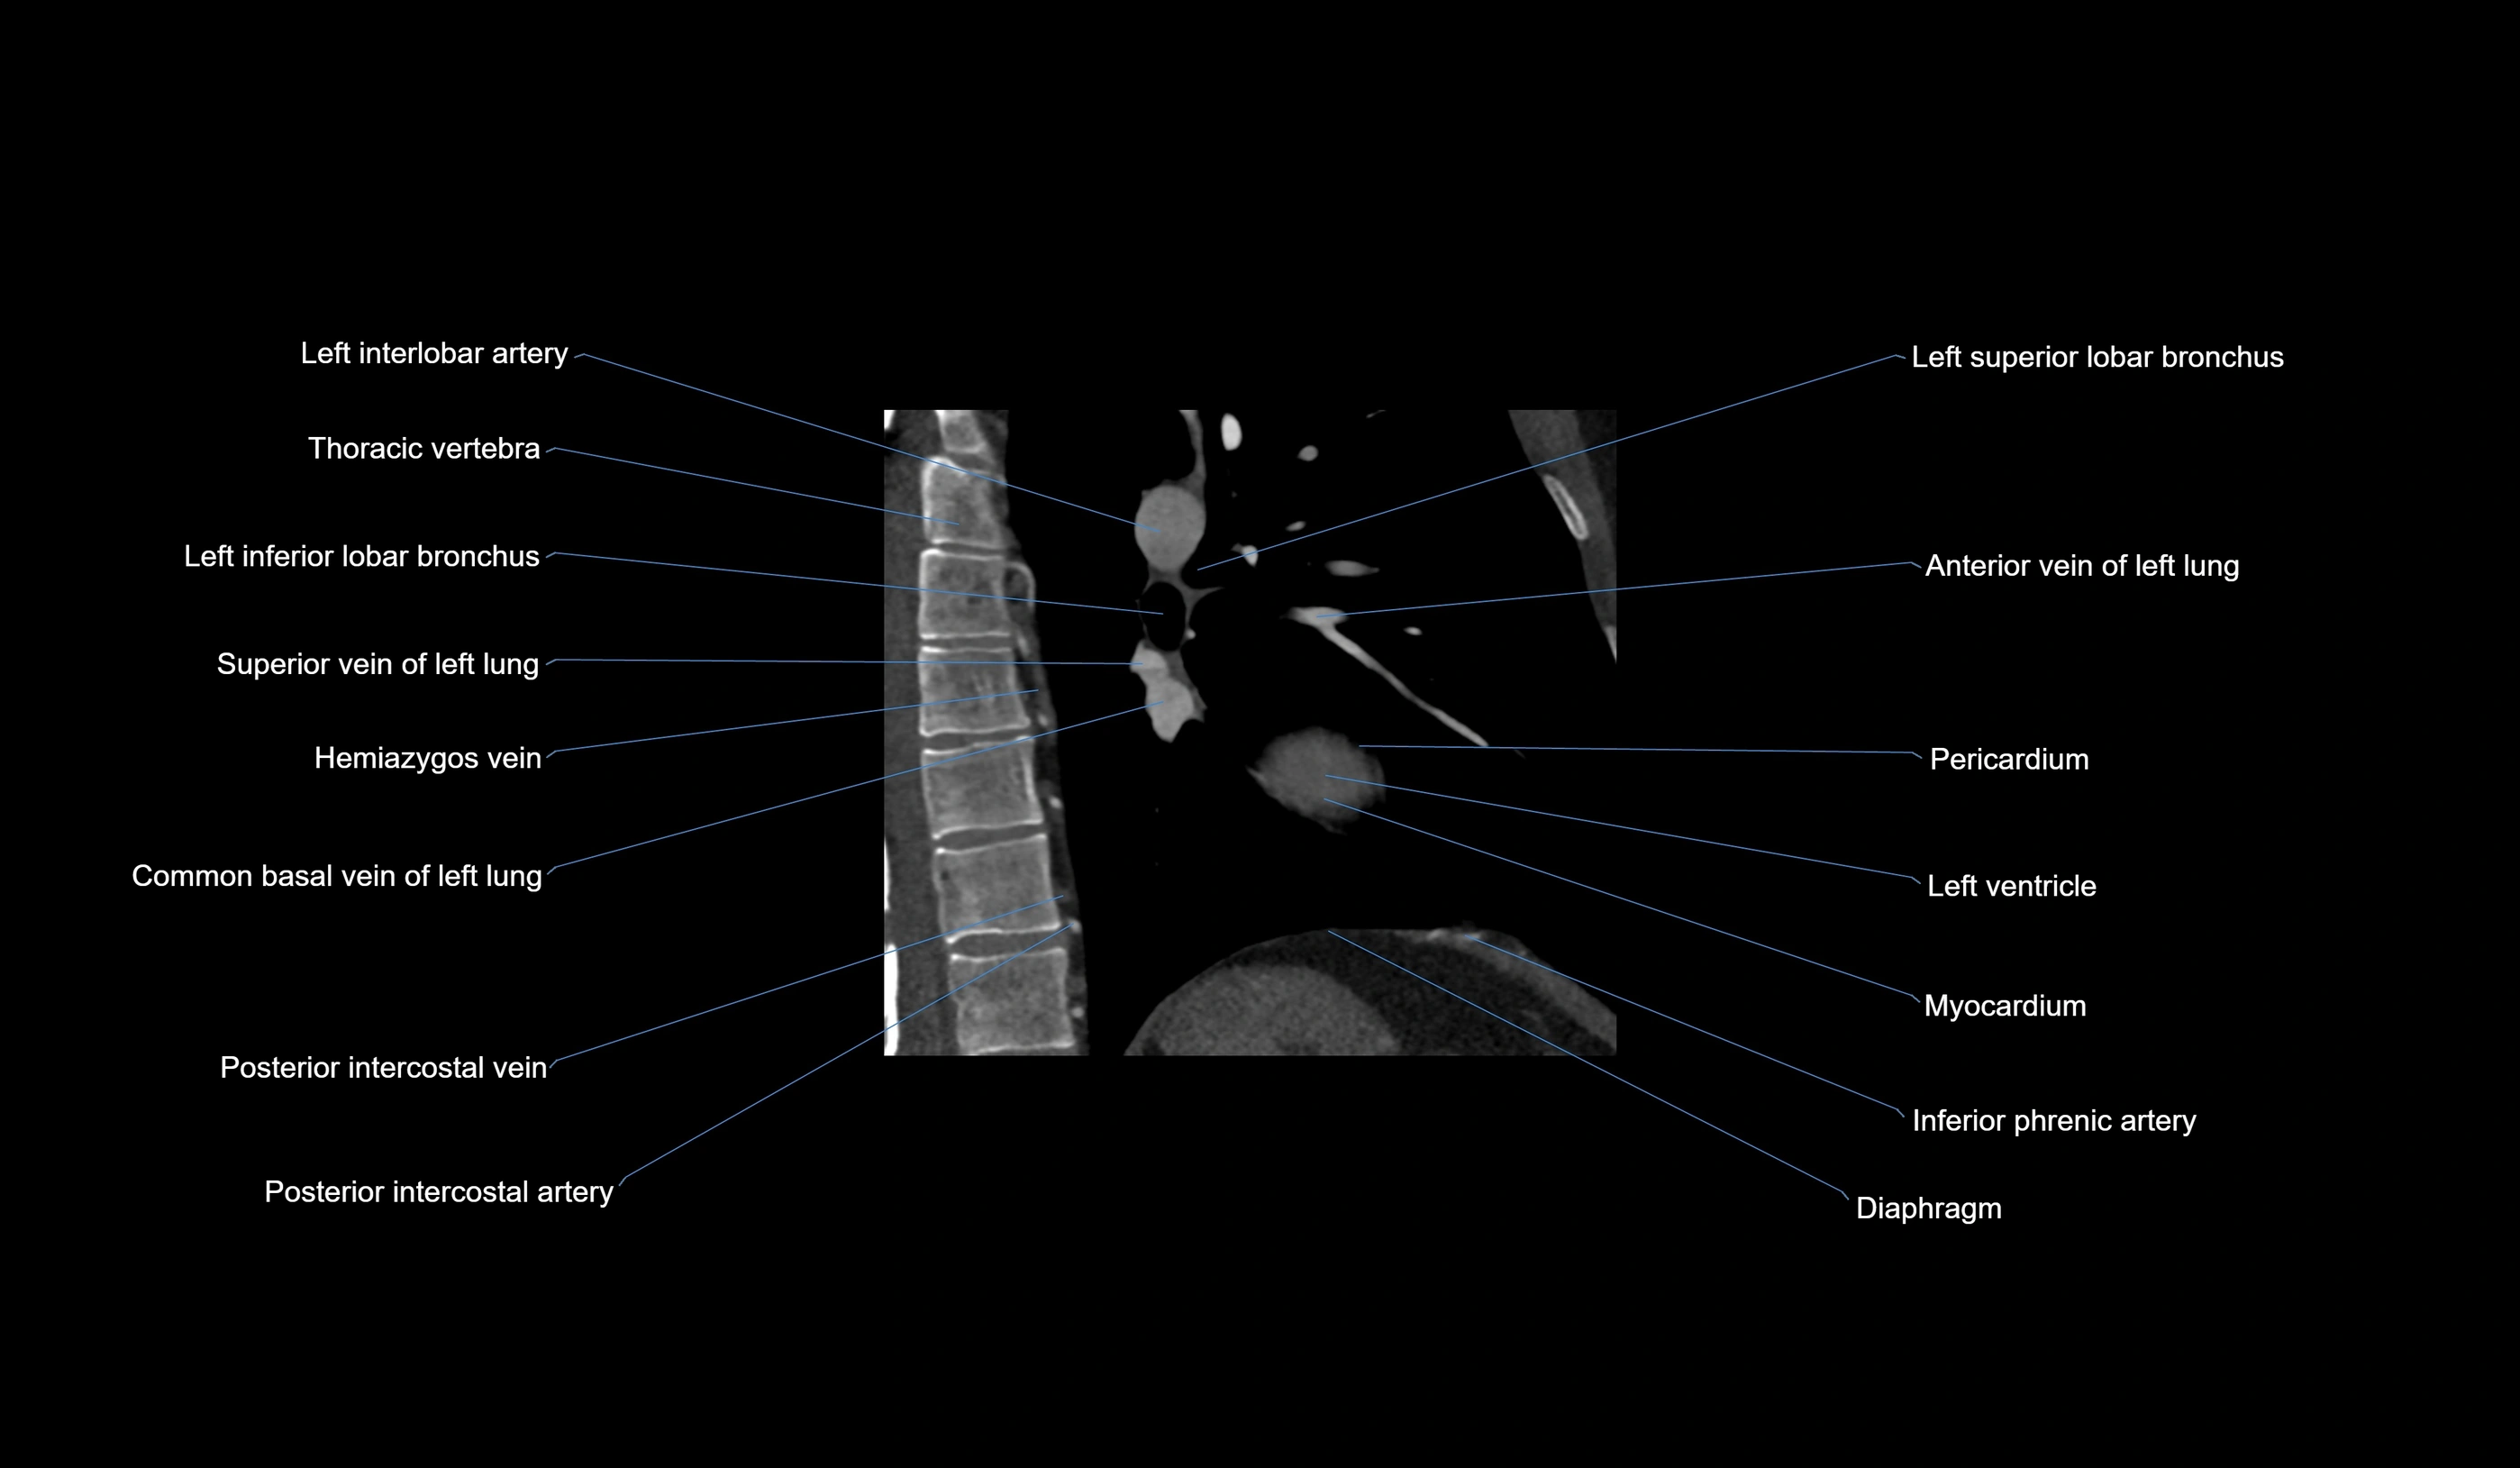

- Left interlobar artery

- Left inferior lobar bronchus

- Left superior lobar bronchus

- Superior vein of left lung

- Anterior vein of left lung

- Pericardium

- Left ventricle

- Myocardium

- Inferior phrenic artery

- Diaphragm

- Posterior intercostal veins

- Posterior intercostal arteries